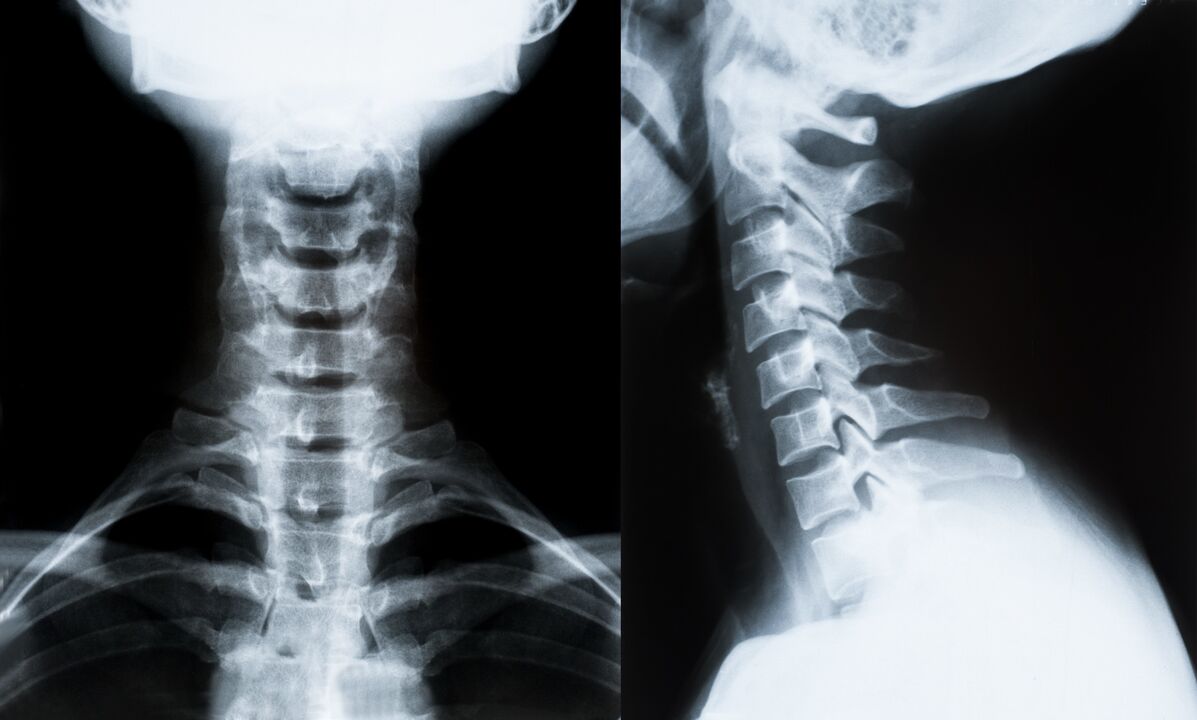

Os principais métodos para diagnosticar e determinar aínda máis o tratamento da osteocondrose da columna cervical:

- Roentgen. O método de diagnóstico menos efectivo, pero tradicional.

- A resonancia magnética é o método diagnóstico máis eficaz. Con este tipo de exame do paciente, todas as estruturas necesarias son visibles.

- Se hai que medir cambios, utilízase unha tomografía computarizada. Determina a presenza de hernias e outras cousas.

- O último método é o exame dúplex de ultrasóns. Este método de investigación determina a velocidade do fluxo sanguíneo nas arterias.

É imposible determinar con precisión unha enfermidade da columna na casa.